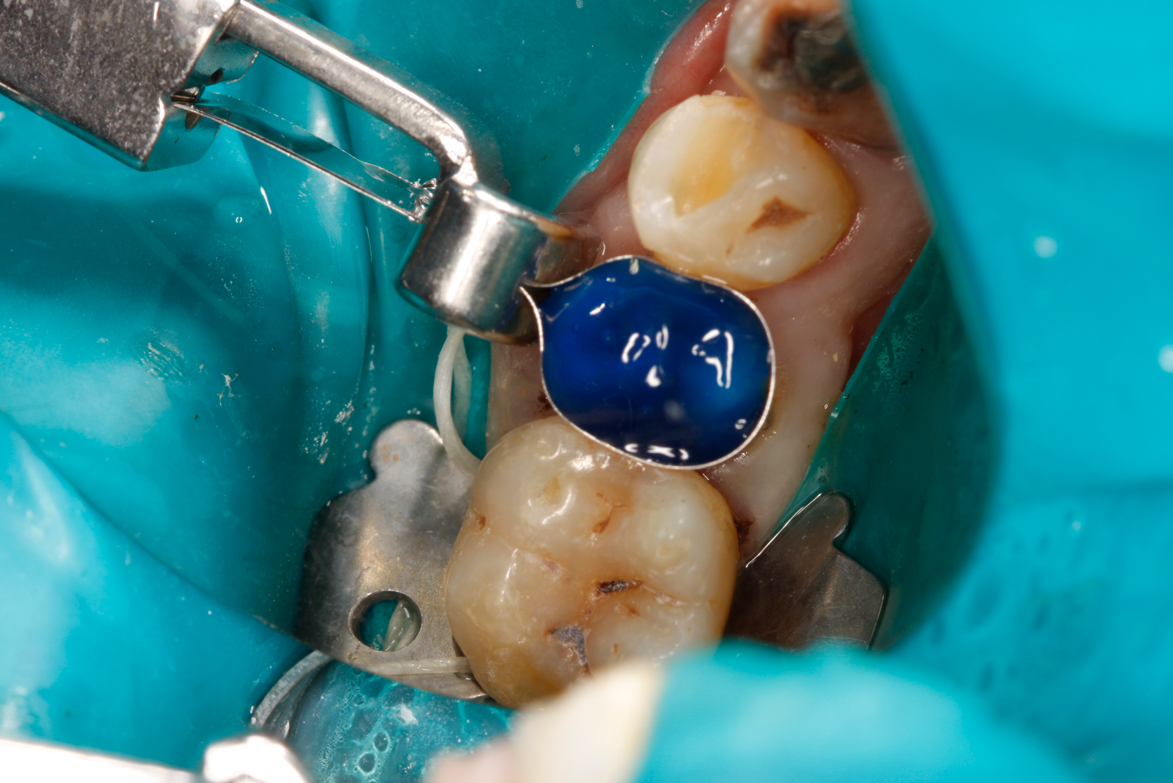

When applying the dual-cured bulk-fill composite, a slight overfill of the cavity prep is important, as stress relief of bonded walls and pulpal floor occurs at the expense of the nonbonded occlusal surface. Auto- and dual-cured composites can be used to mitigate polymer stress in high C-factor restorations and thus prevent pain from pulpal floor gapping postoperatively as well as recurrent caries due to micro-gapping at margins. Dual-cured flowable composites have limited ability to hold a matrix band closely apposed to an adjacent tooth. Consequently, it is critical in developing tight proximal contacts to wedge the teeth prior to preparation of the cavity. This is called prewedging (depicted in Figure 5). Another important consideration is the type of ring, wedge, and matrix employed. The wedge must close off the base of the well-fitting matrix band to prevent overhangs. The separation force of the ring is critical to ensure a good contact with the adjacent tooth. Nate Lawson at UAB found that 28 N was the best measured by Instron, while other researchers claim that 8 pounds measured by removal of ring with forceps is the optimal separation force. Another consideration in selection of the ring and wedge is the amount of separation force generated by these devices. Dr David Clark has discussed that "tack welding" the band to the buccal and lingual of the tooth with flowable composite can be accomplished by holding the band in close opposition to the adjacent tooth with either a matrix adjusting instrument (Bioclear Push-Pull, Bioclear Matrix Systems) or contact-forming instrument (Contact Pro, CEJ Dental) (alternatively: Perform Contact Former, Practicon Dental) (David Clark, DDS, personal communication, December 7, 2022). This does involve using an assistant to light-cure the tack weld; however, it is guaranteed to generate a tight contact (Figure 6 and Figure 7).

Fig 5. Preoperative wedging to create tight

contacts. (Photograph courtesy of Richard

Young, DDS.)

Figure 5

Fig 6A. Push-pull technique with (A) Contact Pro (CEJ Dental) contact-forming instrument and (B) Bioclear Push-Pull (Bioclear Matrix Systems) matrix adjusting

instrument (alternatively: Perform Contact Former, Practicon Dental).

Fig 6A

Fig 6B. Push-pull technique with (A) Contact Pro (CEJ Dental) contact-forming instrument and (B) Bioclear Push-Pull (Bioclear Matrix Systems) matrix adjusting

Fig 6B

Fig 7. Tack welding matrix on buccal and lingual with flowable to ensure tight contact.

Figure 7